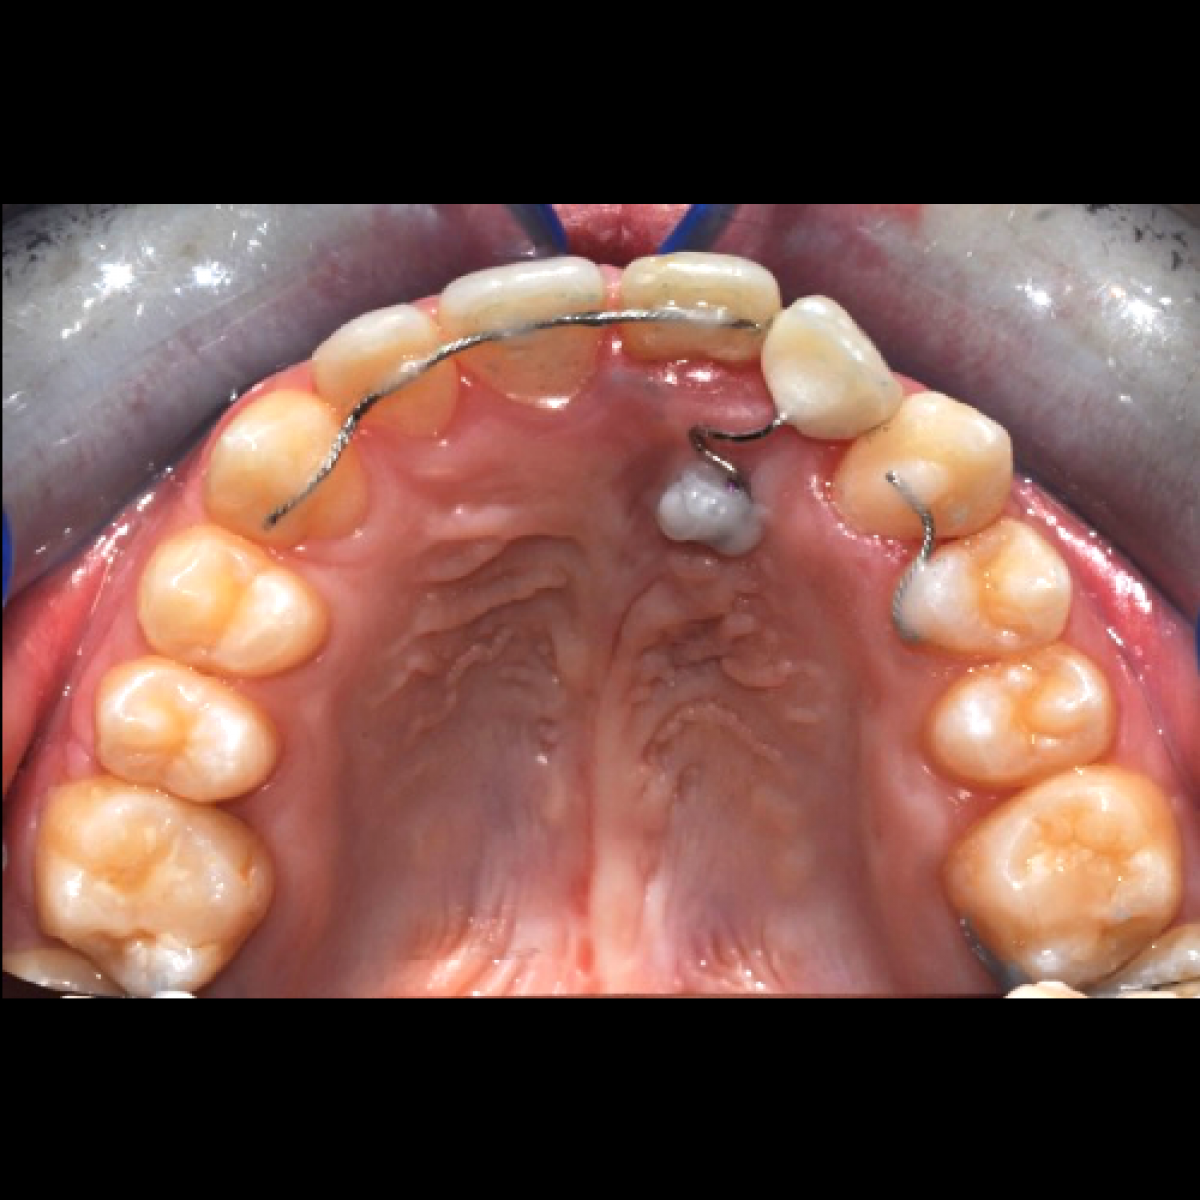

The miniscrew was placed in the site of agenesis, parallel to the occlusal plane, with a palatal to vestibular direction, under local anesthesia, mepivacaine 2% with vasoconstrictor (adrenalin).

A stainless steel sectional wire 0.021 x 0.025 was inserted into the slot of the miniscrew; the wire supported a temporary prosthetic tooth.

By means of a stailess steel ligature (0.012inch) the wire was ligated tightly to the bracket-like head of the miniscrew. The head was covered with flowable composite (Tetric EvoFlow, Ivoclear Vivadent, Casalecchio di Reno -Bologna-, Italia) for comfort reasons. The patient was instructed in using chloirexidine spray, three times a day for ten days after the miniscrew placement..

An upper fixed retainer was placed on elements 1.3-1.2-1.1 and on 2.3-2.4. The patient was instructed in daily flossing between the prosthetic tooth and the mucosa, to avoid gingival inflammation.